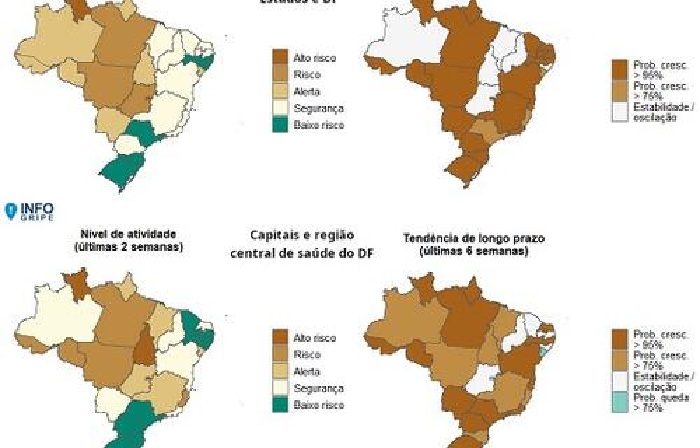

Geral Saúde

InfoGripe: 12 das 27 unidades federativas apresentam incidência de SRAG em nível de alerta

Aumento de Síndrome Respiratória Aguda Grave (SRAG) foi apontado nas regiões Norte e Centro-Oeste, sendo impulsionado em grande parte pelo …

Geral Saúde

InfoGripe: 12 das 27 unidades federativas apresentam incidência de SRAG em nível de alerta

Aumento de Síndrome Respiratória Aguda Grave (SRAG) foi apontado nas regiões Norte e Centro-Oeste, sendo …